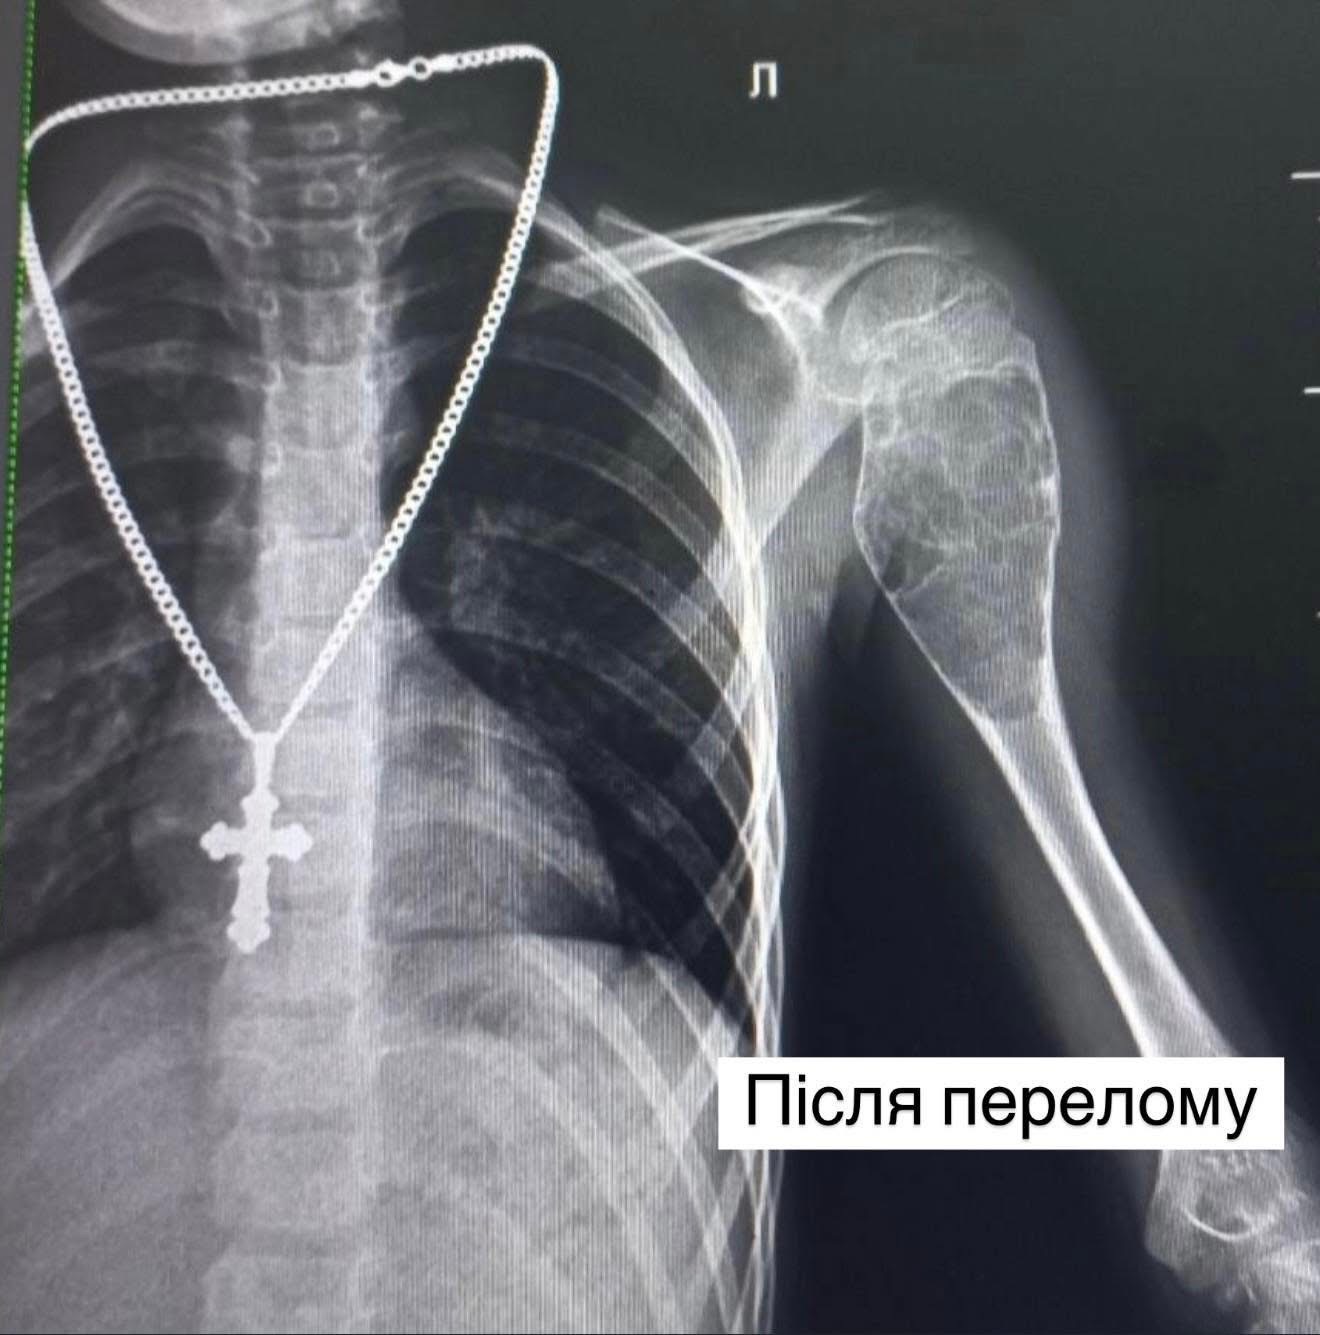

Ортопеди-травматологи Центру дитячої медицини у Львові провели унікальну операцію 10-річному Іванові з Тернопільщини, у якого впродовж двох років ставалося вісім переломів лівої плечової кістки. Про це повідомили у Центрі дитячої медицини «Охматдит».

Причиною виявилась аневризмальна кіста – рідкісне пухлиноподібне утворення, що вражає кістку і робить її надзвичайно крихкою.

З 2022 року життя дитини перетворилося на постійний страх: навіть легкий удар чи рух міг спричинити черговий перелом.

Лише у Центрі дитячої медицини лікарі змогли правильно діагностувати проблему та провести складну операцію — внутрішню резекцію кістки з видаленням пухлини розміром 9×4 см, заміною дефекту аллотрансплантатами та фіксацією титановими стержнями.